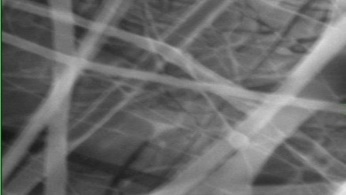

Morphology, size and size distribution of the nanofibres

Morphology analysis was adapted from Aytac et al. (2019) [38]. The SEM analysis was conducted to detect electrospun nanofibers' fibre shape and diameter. The electrospun nanofibres from 18 runs were investigated individually by SEM (FEI, quanta 450, Czech). Images revealed the morphology of resultant nanofibers and measured their diameters in nanometres. The average number of records was calculated using a standard deviation estimation. The setting of the SEM machine was conducted on voltage 25.00 kv, magnification 23624 and width (8.3-9.3 mm).

Results of the SEM analysis are listed in table 2, with a wide range of fibre diameters starting from 87.2 nm (run 13) to 2500 nm (run 18). Run 18 did not produce true nanofibers due to the deficient concentration of PVA. The statistical analysis revealed that the effect of each polymer (factor) on the diameter size of the electrospun nanofiber was vast. Therefore, there is a correlation between factors A, B and C and fibre diameter as expressed in equation 5.

Fig. 3: Nanofibres SEM images with nanofiber diameter frequencies. The PVA, PEO and HPMC were symbolised as V, E and P. Data are given in mean±SD, n=3

The morphology of nanofibers would be affected by device parameters such as flow rate, voltage and distance from the collector. Also, nanofibres' properties could be changed due to temperature and humidity. The bead formation appears with a low concentration of PVA (run 2) or a high concentration of PEO and HPMC (runs 6 and 11), as shown in fig. 3. Therefore, increasing PVA concentration leads to beads' disappearance and smooth fibres' formation. Nageeb El-Helaly (2021) and Silva J. A. et al. (2021) reported similar results [47, 48]. Kalluriet al.(2021)[49] studied the relationship between the fibre diameter, bead diameter and flow rate. Thus, they concluded that better fibre uniformity and bead formation were needed at a high flow rate. These results appear clearly in run two and run six and agree with Silva et al.(2021) results [50], who reported that only the concentration of PVA (≥ 15%) could produce uniform nanofibers when using the lower molecular weight of PVA (67,000). Fibre diameter of 15% PVA and more appeared to be in the range 87.11 to 252.5 nm with uniform fibres and disappearance of beads except in run 6, where the beads appear due to increasing the concentration of HPMC as highlighted by Gripet al. (2018) [46].